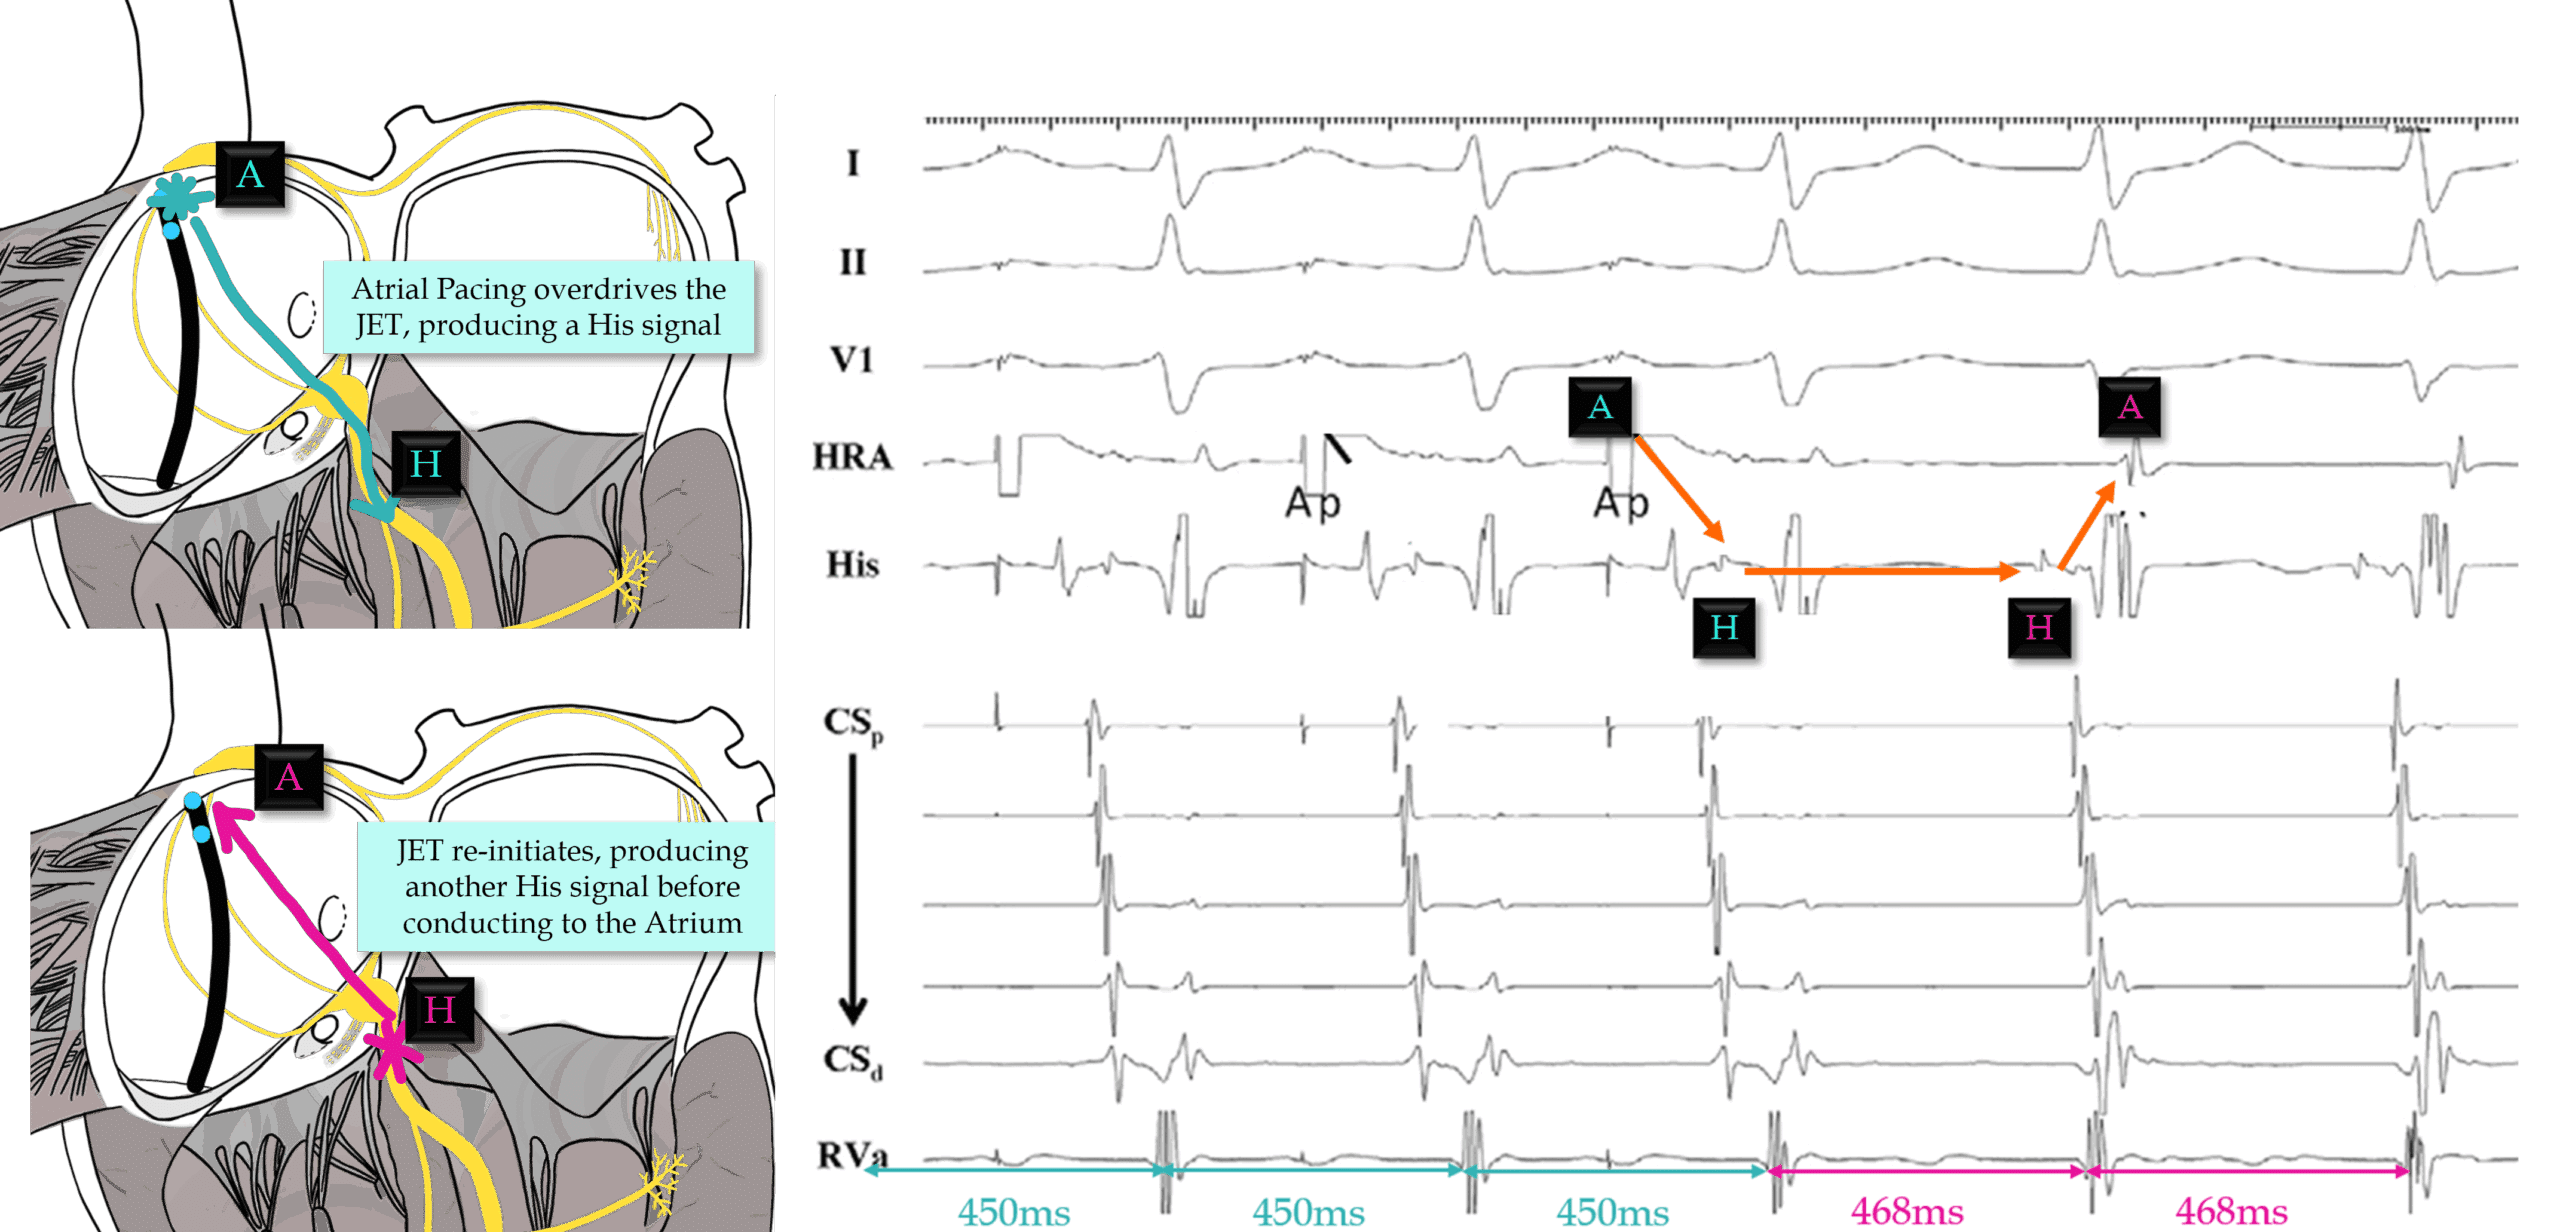

Answer: This EGM is diagnostic of a focal arrhythmia arising from the His Bundle/AV node due to an AHHA response following successful atrial overdrive pacing, consistent with Junctional Ectopic Tachycardia.

Pacing the atrium 20ms faster the the TCL is useful in differentiating JET from AVJRT in patients with 1:1 AV conduction.

You must accelerate tachycardia to your pacing cycle length and the tachycardia must continue at it’s original TCL.

1. An AHHA response is diagnostic for JET.

2. An AHAH response indicates Reentry (AVJRT/AVRT).

Top tip: Always confirm your last entrained His/V signal! Measure it, don’t assume it.